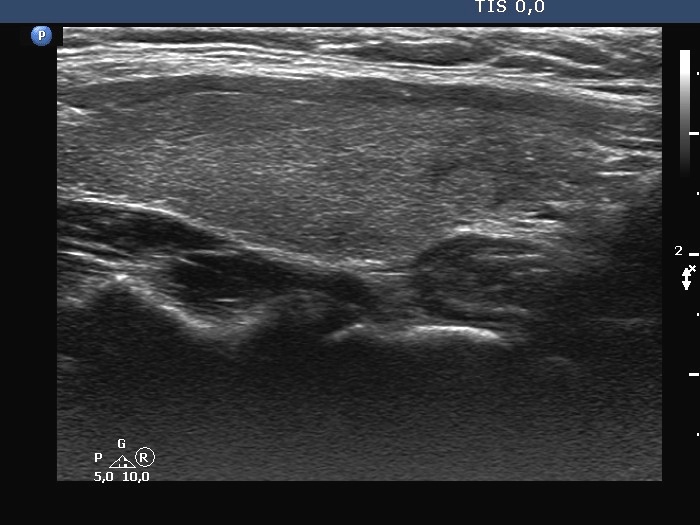

TIRADS - case 2111 (ultrasonographic picture 5)

Left lobe, longitudinal scan.